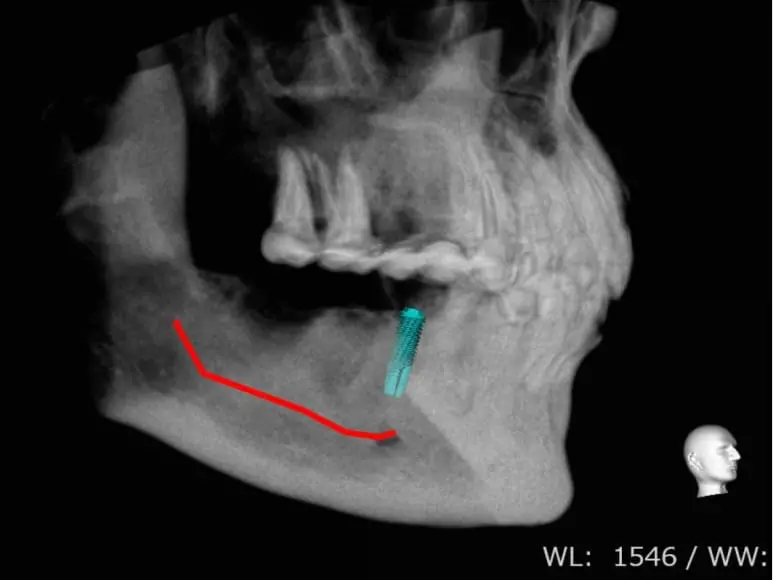

CTスキャンのデータと連携し、顎の骨の立体的なイメージをコンピュータで確認しながらインプラントを埋める位置を決定し、決めた位置に正確にインプラントを埋め込むことができるオステム社のシステムです。

傷口が最小限で済むので、患者さまの負担を最小限にすることが可能です。

3Dによる画像診断・治療計画

CTで撮影したデータをもとに立体的に顎の骨を確認し、顎の骨の内部にある神経、血管などの状態を詳しく確認して診断を行い、治療計画のご説明をいたします。

インプラント埋め込みのシミュレーション

コンピュータの画面上でシミュレーションソフトを使い、立体的な顎の骨のイメージに合わせてインプラントの埋め込み場所を決定します。